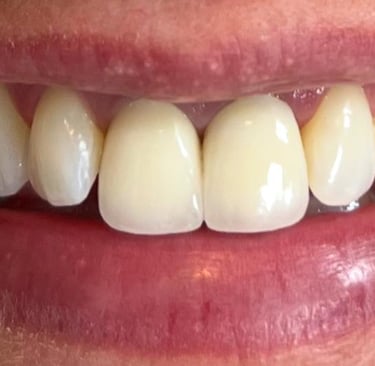

Aspecto Clínico Final - Fotografias originais — nenhuma contém retoques — A cor dos dentes é escolhida de acordo com o gosto e a preferência estética de cada paciente.

Coroas em Dissilicato de Lítio

Todos os caso a seguir estão associadas a clareamento dentário